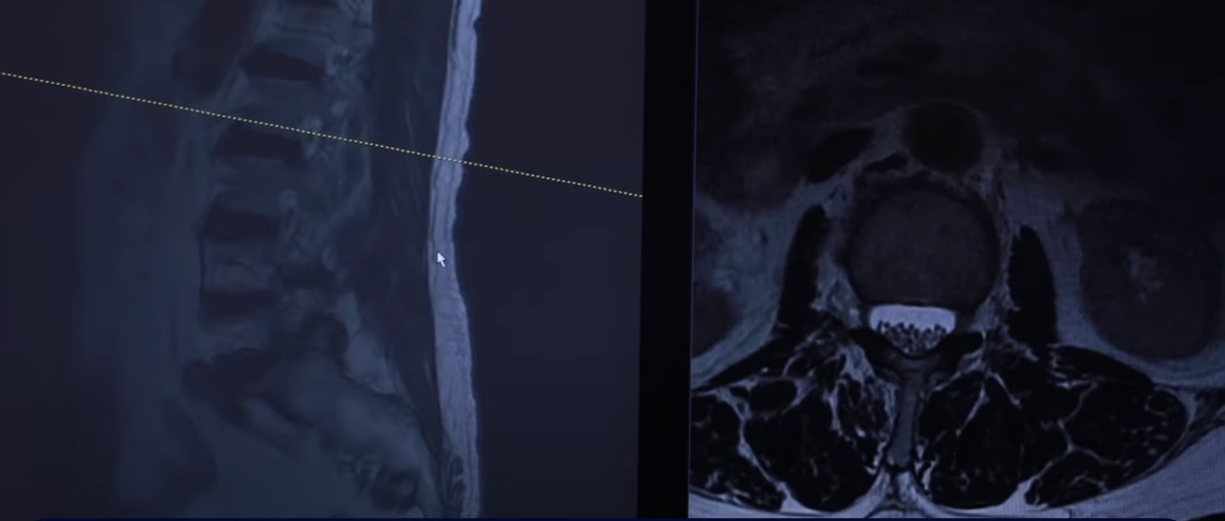

73세 여자 협착증 전방전위증 환자분 MRI 보시겠습니다. 보시다시피 여러 마디의 퇴행성 디스크가 있습니다.

근데 이분 증상은 왼쪽 다리가 너무나 심하게 아파서 걸을 수도 없고 그래서 절뚝거리면서 걷는 분입니다. 이분 두 마디가 특히 안 좋으신데요. 보시다시피 4번 5번 굉장히 척추관도 좁아져 있습니다. 그리고 이게 왼쪽 신경입니다. 왼쪽 신경이 나가는 구멍이 좀 좁아져 있습니다.

그런데 왼쪽 신경이 나가는 구멍이 훨씬 더 좁은 곳은 5번 1번 이 마디입니다. 아주 까맣게 보이죠. 오히려 척추관협착증은 이 마디가 덜 심한데 이 신경 나가는 구멍, 왼쪽으로 나가는 구멍은 이렇게 심하게 막혀 있습니다.